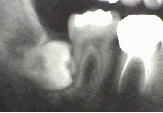

生えかたの違う親知らずのレントゲン写真を幾つかご覧に入れます。

親知らずが生えるスペースが不足すると、斜めに生えて半分しか顔を出せません(半埋伏といいます)。これでは歯と歯茎の間に歯垢が蓄積して細菌感染し炎症をおこしやすい状態で、「智歯周囲炎」とよばれています。また虫歯にもなりやすく、中等度以上の虫歯では抜歯以外に治療法はありません。抜歯するには歯の切断を要する場合が多いです。

あごの骨の中に完全に埋まっている状態。しかも水平に倒れています(水平埋伏)。この状態で、「智歯周囲炎」をおこした場合には歯ぐきを切開し親知らずを覆っている骨を一部取り除いて抜歯する必要があります。やや困難な処置になります。抜歯後に腫れや痛みが出る場合が多いのはこのタイプです。